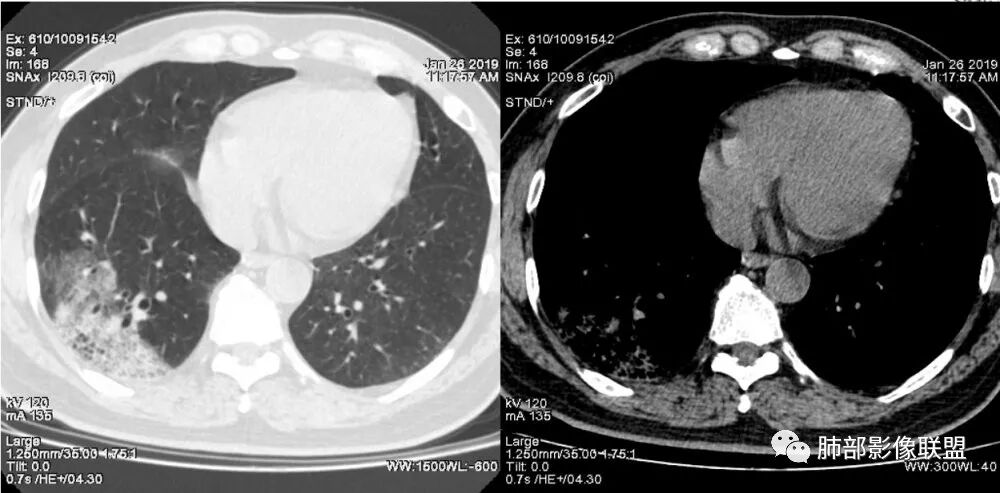

老年女性,咳嗽咳痰病史,右肺下叶大片磨玻璃实变影,胸膜下分布,支气管进入后扩张、僵直,磨玻璃影边界清楚,考虑粘液腺癌。鉴别肺炎。

右肺下叶基底段靠胸膜实变/磨玻璃混杂密度影,边界清楚,内见多发空泡(蜂窝样趋势改变?); 临床:咳嗽咳痰,无发热、胸痛; 考虑腺癌:无发热,感染性病变不首先考虑;部分层面形态类楔形,鉴别肺栓塞

老年人,右肺下叶斑片状阴影,病灶有膨胀性,边缘可见磨玻璃影,其边界清晰,内见僵硬的支气管,部分支气管扩张,首先考虑占位性病变,粘液性腺癌可能。鉴别感染性病变,后者边缘多有收缩性改变或者平直,内部支气管走形自然。

中年女性,右肺下叶沿胸膜下大片状高密度影,实变加GGO,外朝内发展,边界较清,内可见蜂窝征及枯树征,考虑肺炎型肺癌。

右肺病灶,病灶较大,实性+周边ggo,边界清晰,胸膜下分布,长轴平行于胸膜,内部支气管充气征,因不发热,暂不考虑感染性病变,支持肺炎型肺癌。

女性,咳嗽咳痰不发烧,右下外基底段实变影,边缘清楚GGO,有充气支气管征,枯树枝不明显,由外向内;诊断:肺炎型肺腺癌;鉴别:1、肺栓塞(外型神似,但无胸痛丶咯血);2丶肺炎

老年女性,咳嗽、咳痰。右肺下叶沿胸膜下大片状高密度影,外周磨玻璃影,边界较清,小空泡,蜂窝征及支气管充气征,叶间裂串珠征,考虑:肺炎型肺癌,鉴别:肺克,链球菌,NTM等感染。

右肺下叶胸膜下大片状MGGO,其内结构紊乱,可见空泡征,病灶内近端支气管扩张,远端闭塞,形态不规则,边界部分清楚,部分似清非清,考虑粘液腺癌,鉴别淋巴瘤

1.本例病灶较大片混杂密度影,胸膜下分布为主(未沿着支气管分布),该分布特点可见于大叶性肺炎、干酪性肺炎、淋巴瘤及粘液腺癌等。可惜未提供增强扫描图像。

2.病灶示中央实变区,周围GGO,可见明显小叶间隔增厚,GGO边界清楚,应当考虑到恶性病变的可能性。肺炎因炎性水肿及渗出,影像上边界常模糊不清,注意早期粘液腺癌可出现似清非清的边界。粘液腺癌因粘液成份较多,密度一般偏低,纵隔窗病灶常会消隐或范围会明显缩小,这不同于炎性实变。

3.病灶内支气管走形略显僵直,侧支少(粘液阻塞),也符合肺腺癌的枯树枝征。而大叶性肺炎的支气管是管壁光整、通畅、自然,结核的支气管常常壁增厚,甚至狭窄后扩张;